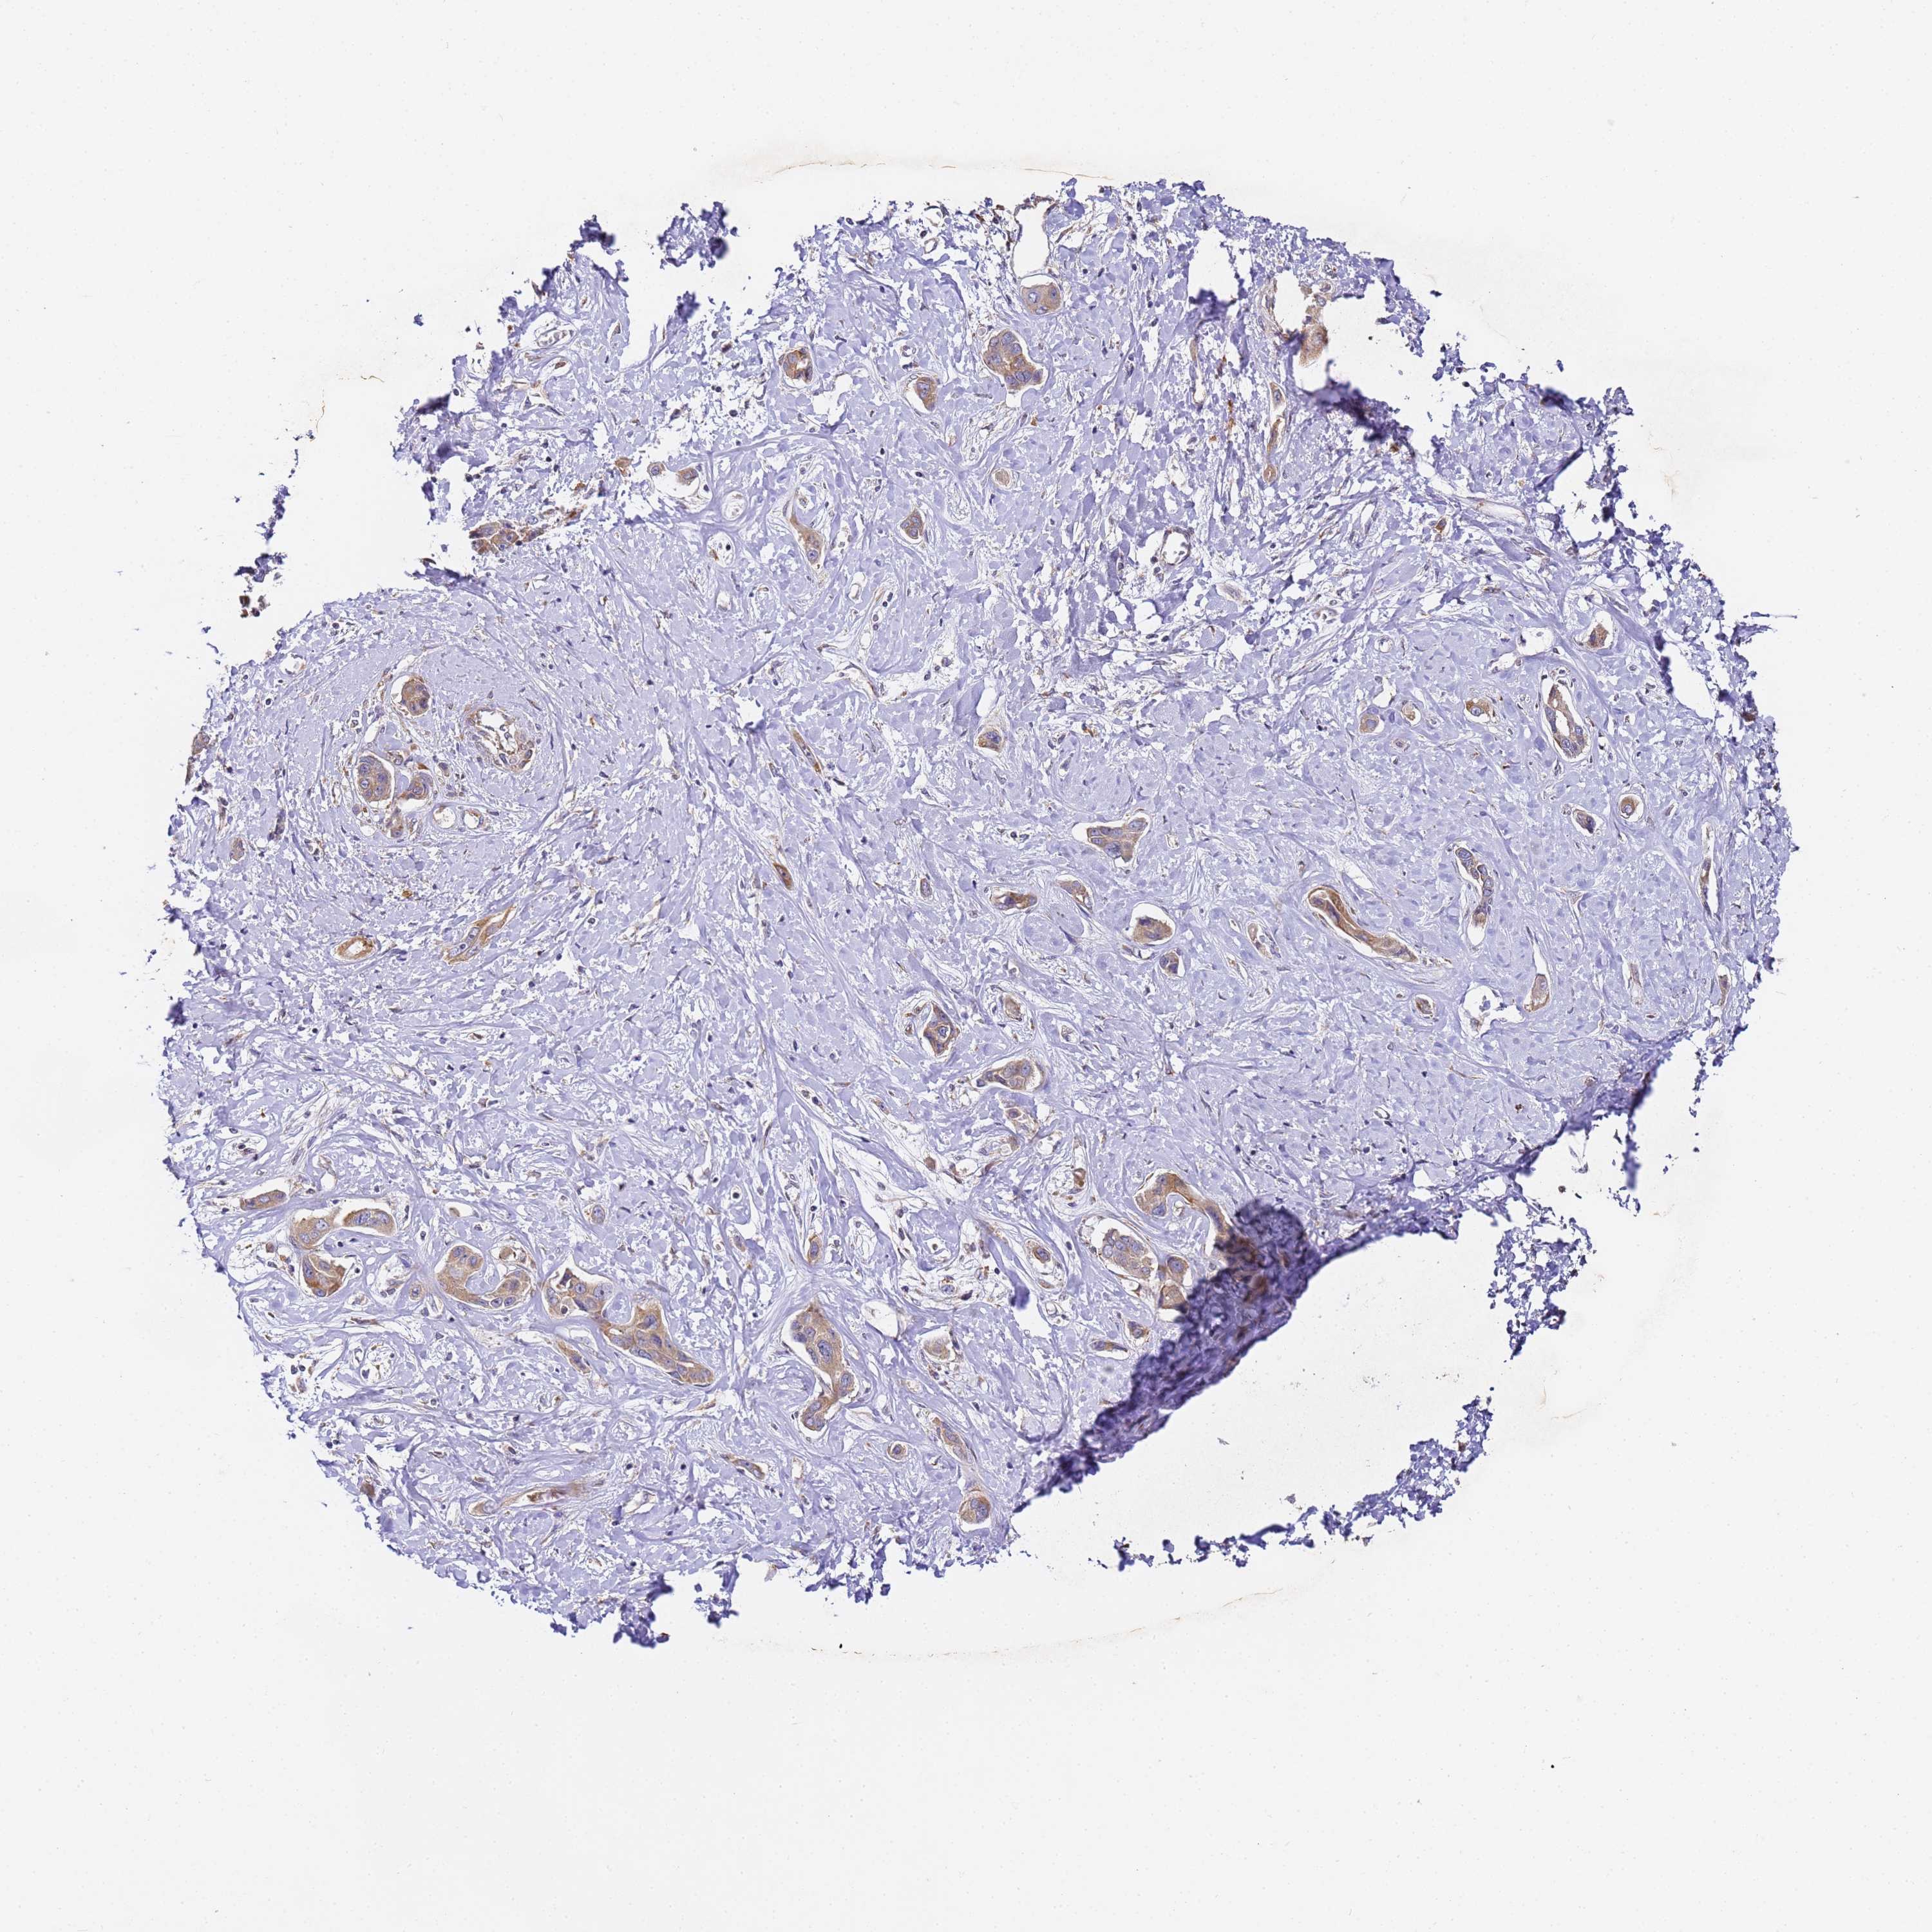

LIVER CANCER - Protein expressioni

A mouse-over function shows sample information and annotation data. Click on an image to view it in a full screen mode. Samples can be filtered based on level of antibody staining by selecting one or several of the following categories: high, medium, low and not detected. The assay and annotation is described here.

Note that samples used for immunohistochemistry by the Human Protein Atlas do not correspond to samples in the TCGA dataset.

Antibody stainingi

Antibody staining in the annotated cell types in the current human tissue is reported as not detected, low, medium, or high, based on conventional immunohistochemistry profiling in selected tissues. This score is based on the combination of the staining intensity and fraction of stained cells.

Each image is clickable and will lead to virtual microscopy that enables deeper exploration of all samples and also displays staining intensity scores, fraction scores and subcellular localization as well as patient and tissue information for each sample.

Antibody HPA038751

Staining

High

Medium

Low

Not detected

Intensity

Strong

Moderate

Weak

Negative

Quantity

>75%

75%-25%

<25%

None

Location

Nuclear

Cytoplasmic/membranous

Cytoplasmic/membranous,nuclear

Cholangiocarcinoma

Carcinoma, Hepatocellular, NOS